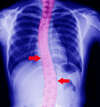

La scoliose, l'attitude scoliotique

Lorsque la colonne vertébrale n'est "pas droite" vue de face et en fonction de l'importance de l'angle de la courbure (ou des courbures) on parle de scoliose ou d'attitude scoliotique.

Même si à l'examen chiropratique on peut constater une scoliose ou attitude scoliotique, le bilan radiologique permettra de poser le diagnostic de scoliose et apportera des informations spécifiques à chaque scoliose, importantes pour le suivi.

traitement scoliose

radio thoracique scoliose chiropracteur paris

nb: Sur cette radio on observe une scoliose en forme de "S"